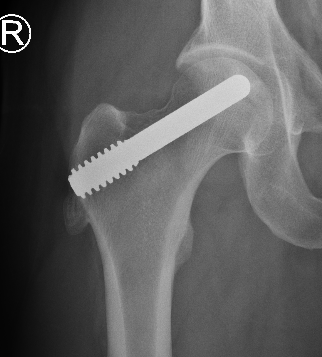

1. Central core decompression through femoral neck

Central Core Decompression Techniques

Zimmer PerFuse Percutaneous Decompression System

Technique

- AP and lateral xray

- entry point through greater trochanter

- above lesser trochanter to reduce fracture risk

- enter site of AVN

- overdrill

- +/- bone graft / vascularized bone graft / tantalum rod / BMAC (bone marrow aspirate concentrate)